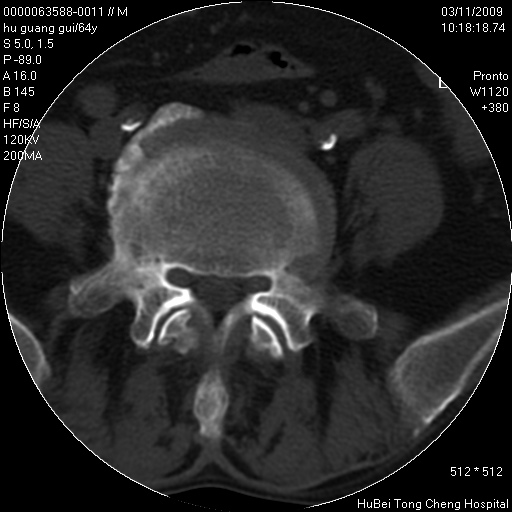

患者 男,64岁。腰痛十余天。(临床未提供其他病史)

临床诊断:腰痛原因待查(腰椎间盘突出症?)。

腰椎间盘ct轴位平扫(层厚5mm,层距4mm),图像如下:

腰椎退行性变,腰4—5椎间盘膨出。

右侧骶骨侧块骨侵蚀,骶髂关节骨性关节面破坏,并见软组织肿块,考虑骨转移瘤可能,进一步检查。

1.腰椎退行性变,腰4—5椎间盘膨出。

2.右侧骶骨侧块骨侵蚀,骶髂关节骨性关节面破坏,并见软组织肿块,考虑:脊索瘤,骨转移瘤可能,进一步检查。

1)腰椎退行性变,l4—5椎间盘膨出。2)骶骨右侧块骨转移瘤可能,3)水平骶椎。建议作一步检查。